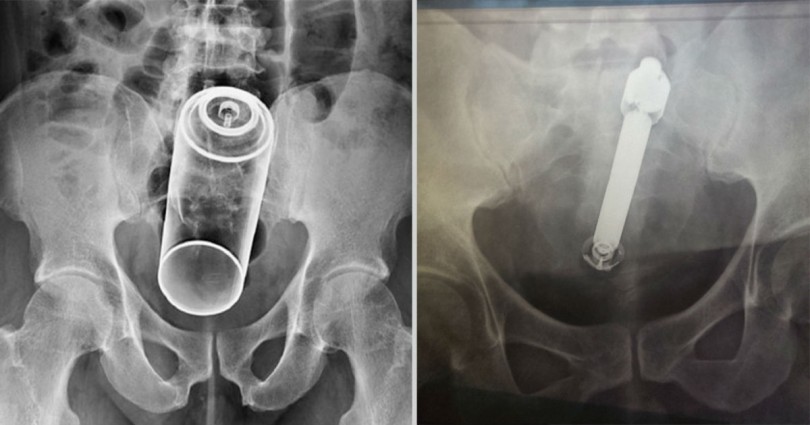

17. Ένα oμοίωμα ανδρικού μορίου